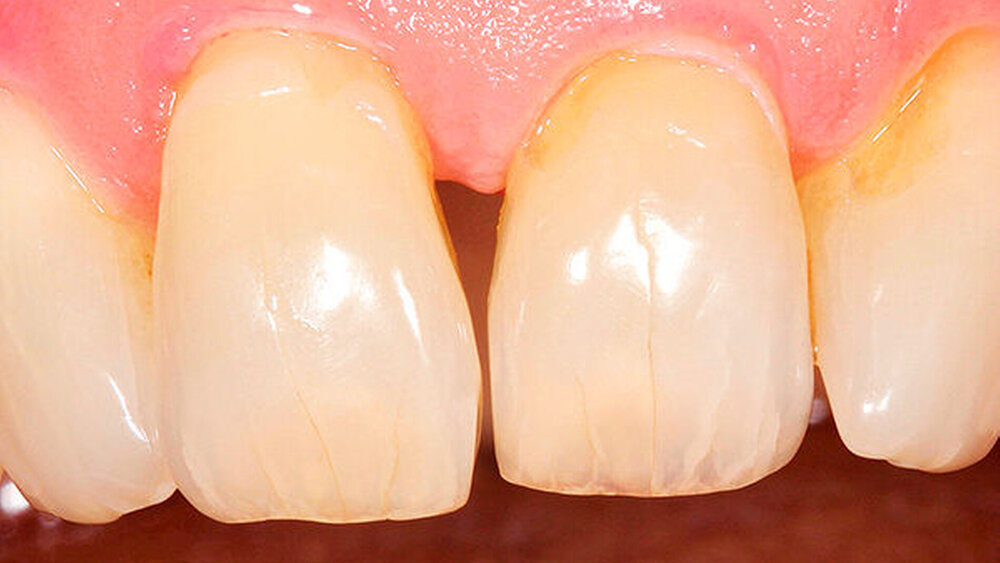

Wie genau managen Sie die prothetische Versorgung?Hermann:Der Anwender kann auf die gewohnte CAMLOG oder CONELOG Prothetik zurückgreifen. Die Entscheidung für die konische oder flache (Butt-Joint) Schnittstelle bietet dem Anwender die Möglichkeit, mit ein und demselben Implantatkörper das Implantat entweder epikrestal oder leicht suprakrestal zu positionieren. Diese Wahlfreiheit kann bei Versorgungen etwa in ästhetisch anspruchsvollen Regionen eine Rolle spielen. Aufgrund der konischen Innenverbindung und des integrierten Platform Switch eignet sich das CONELOG PROGRESSIVE-LINE für eine subkrestale Positionierung.

Ihr Fazit? Hermann:Zusammenfassend kann ich sagen, dass wir mit der CAMLOG PROGRESSIVE-LINE eine Erweiterung der klinischen Indikationen in Bezug auf eine simultane Vorgehensweise (Implantation und Augmentation kombiniert) beobachtet haben, und zwar aufgrund der bereits erwähnten Primärstabilität bei schwierigen anatomischen Situationen. So können wir in vielen Fällen auch eine Sofortversorgung/Sofortbelastung des Implantats in Erwägung ziehen. Die situative Adaptation des Bohrprotokolls verschafft uns eine effiziente Insertion, die vorhandene, bewährte Prothetikschnittstelle der Implantate von CAMLOG das vertraute Handling, und dies alles bei einem Implantat, das wir bei allen klinischen Situationen zum Einsatz bringen konnten.